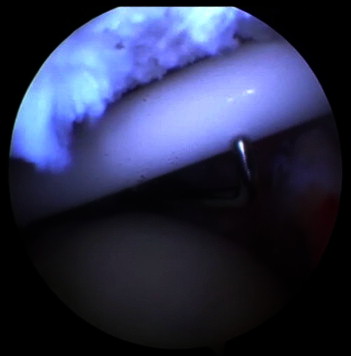

Figure 5.

Assistance in spacer (balloon) deployment using probe in left shoulder with patient in beach-chair position, arthroscope in posterior portal, and arthroscopic probe in anterior portal.